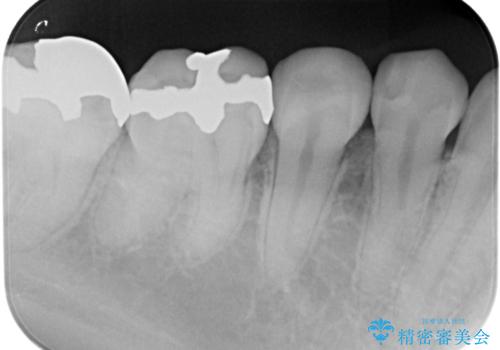

レントゲンで見つかった歯と歯の間の虫歯をセラミックインレーで修復

- 定期検診でレントゲンを撮ったら虫歯(カリエス)があったため、e-maxインレーにて治療しました。

治療した歯は過去に樹脂で治療されていて、虫歯が再発していました。

樹脂の治療は経年的に劣化し、また歯質との隙間ができて虫歯の再発リスクが高いです。

e-max(セラミック)の治療は劣化をせず、歯質との隙間もできないため虫歯の再発のリスクが低いです。